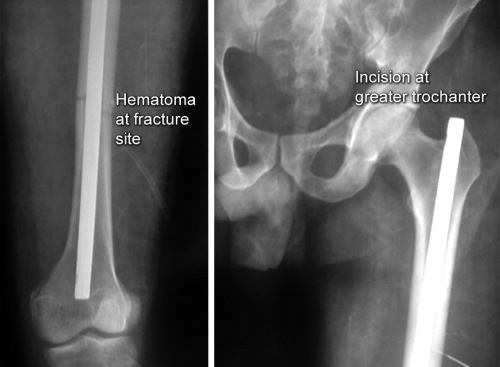

However, in some special situations internal fixation can also be done in some fractures that have been reduced closed [e.g. while nailing a long bone (Fig. 1.40)]. Here the treatment is called as closed reduction and internal fixation (CRIF) as skin incision being away from fracture site does not drain the hematoma (so closed reduction) while the fracture is fixed with an implant that lies inside the skin (internal fixation).

It was a V-shaped steel nail which was later changed to hollow clover leaf model. This nail relied on a frictional fit between nail and bone. Since then intramedullary nailing has seen many changes in design as well as in technique. In 1942, Fischer introduced the use of intramedullary reamers to increase the contact area between the nail and host bone thus increasing the stability of fracture. Later Modney invented the interlock nails that get locked in bones to provide additional rotational stability in case of comminuted fractures (Fig. 1.44). Then in the 1960s, development of image intensifiers allowed surgeons to do intramedullary nailing with better confidence and with closed reduction (as explained in Fig. 1.40).

Principle of intramedullary nailing: Fracture is reduced under image intensifier and after reaming of medullary cavity nail is inserted into the medullary cavity which act as an internal splint to resist bending. Interlocking nails are provided with slots for locking bolts which prevent rotation and shortening.

Advantages of intramedullary nailing: It is ideal implant for long bone diaphyseal fractures. It can be implanted by minimally invasive technique without exposing the fracture hematoma. Thus it is a biological method of fracture fixation.